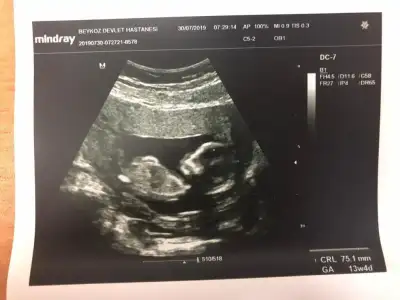

Bebek göstermedi bacak arasını doktor da göremedim kemik yapısından kıza benzetiyorum görmeden yüzde yüZ diyemem dediDoktor ne Tahmin etti

Bu usg ye gore kiz canim nubu zorda olsa gorunuyor paralel gonlundeki olsun ben sadece bu usg ye gore yorum yapiyorum dr daha detayli goruyorBebek göstermedi bacak arasını doktor da göremedim kemik yapısından kıza benzetiyorum görmeden yüzde yüZ diyemem dedi![]()